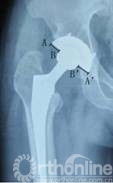

7例术前发现假体周围炎性假瘤患者,均进行聚乙烯磨损和线性磨损率测量。聚乙烯磨损表现在骨盆正位X线片上为聚乙烯内衬不对称(图2),两侧差值为股骨头偏移距离。本组病例股骨头偏移距离为2.00mm~7.12mm,平均3.57mm。

图2  X线片上AB=A’B’,表示聚乙烯无磨损,如果AB≠A’B’,则表示内外侧股骨头不对称,存在聚乙烯磨损